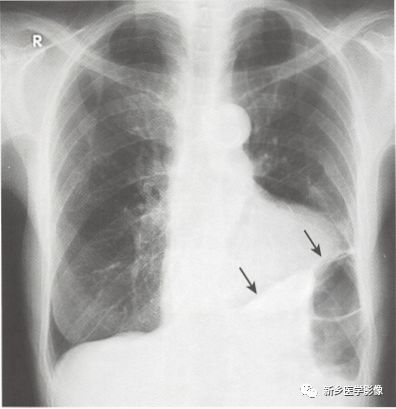

胸水胸片典型图片

胸水胸片典型图片,

当胸腔积液量达到300mi时,外侧肋膈角变钝,在正位胸片,上可见.